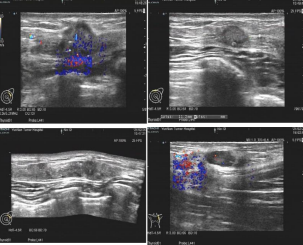

• 乳腺超声:1.左乳上 12 点至外上 3 点多发成片肿物,3.6 cm x 0.9 cm x 2.2 cm,距乳头 3.3 cm,边界不整,内部低回声,分布不均,BI-RADS:5 类,考虑乳腺 CA;2.左乳内上 10 点回声紊乱,1.5 cm x 0.9 cm,BI-RADS:4B 类,恶性不排外;3.左前胸壁及腋窝区域肌层实质占位,考虑软组织转移灶,1.7 cm x 1.2 cm;4.左腋窝腋下组淋巴结,1.4 cm x 0.8 cm,考虑转移。

图片

图 2 乳腺超声结果